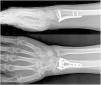

Intervención: Luego de 3 días del trauma se le practicó reducción abierta más osteosíntesis con placa de bloqueo volar (fig. 5). En control de ortopedia a los 15 días del posquirúrgico presenta limitación funcional total de mano y muñeca derecha, ocasionada por el dolor y el edema. Después de 21 días del posquirúrgico inició el proceso de rehabilitación, asistió a 10 sesiones de terapia física y a 11 sesiones de terapia de movilización pasiva con órtesis robótica (fig. 6).

Resultados: inicialmente se encontró una puntuación en la escala DASH de 85.83 y en la escala EVA de 9; después de 4 semanas de rehabilitación complementada por órtesis robótica, mejoró la funcionalidad según DASH a 16.91 y disminuyó el dolor según EVA a 3. Además, mejoró los arcos de movilidad articular de la muñeca en extensión de 25 a 75 grados, en flexión de 30 a 60 grados, la desviación radial de 10 a 30 grados, y la desviación ulnar de 10 a 15 grados. La paciente inició las actividades de la vida diaria luego de la tercera semana de rehabilitación, y no se reportaron eventos adversos durante la intervención. (Tabla V y VI)